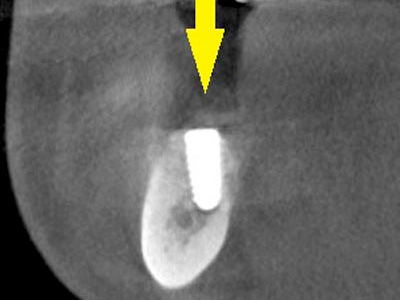

移植した骨が周囲の骨と結合したのを待ち、6か月後にインプラント埋入手術を行いました。

写真がインプラント埋入後のCT画像で、黄色矢印に示すようにインプラントが2本埋入できました。 -

インプラント埋入後の、別な方向からみたCT画像です。

神経の通る管にややギリギリでしたが、神経は傷つけずにインプラントが埋入できました(黄色矢印)。